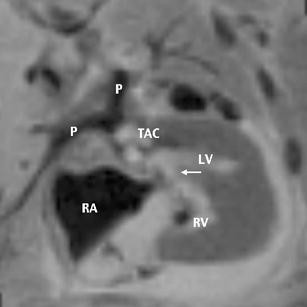

Different techniques are used in fetal cardiology, and their accuracy has been demonstrated on several occasions. Color Doppler US has proved to be a reliable and valuable tool in the diagnosis of fetal cardiac abnormalities. Magnetic resonance imaging (MRI) of the fetal heart has, so far, played no role in prenatal diagnostics. We report on a truncus arteriosus communis diagnosed prenatally during a screening ultrasound at 22 weeks of gestation. In addition to real-time ultrasound and color Doppler echocardiography, fetal MRI was performed. Fetal echocardiography arose suspicion of a type I common trunk. Fetal MR showed solely a widened vessel coursing retrocardially and additionally an inhomogeneous fluid distribution of the lung not shown on prenatal US. After termination of pregnancy at 23 weeks of gestation, MR fetography and autopsy were performed, and both found a type II common trunk. MR autopsy of the heart was very reliable in this case and could be an alternative when fetal pathology is not available for different reasons. Postmortem MRI was also able to demonstrate the inhomogeneous fluid distribution in the lung, which was confirmed by autopsy. Fetal and postmortem MR was reliable in the detection of an inhomogeneous fluid distribution in the lung not shown on prenatal US, providing a relevant additional finding to US. Therefore, MRI should be used more often in fetal cardiology, although it still must be further developed.

Fig. 1

Fig. 2

Fig. 3

Fig. 4

Fig. 5

Fig. 6

Fig. 7

Fig. 8